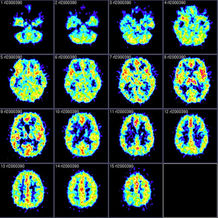

Yes, we've all heard and (most-likely) used the term, "mommy brain." You know, when you're toting around a newborn and do things like lock the keys in the car, drive away with your precious coffee ON TOP your car, or leave the dog tied in front of the store (yes, this actually happened to a friend of mine). We laugh and blame it on our Mommy Brain, but, new research shows that Mommy Brain is a good thing. The article, which is on the American Psychological Association's website, states that, "The researchers performed baseline and follow-up high-resolution magnetic-resonance imaging on the brains of 19 women who gave birth at Yale-New Haven Hospital, 10 to boys and nine to girls. A comparison of images taken two to four weeks and three to four months after the women gave birth showed that gray matter volume increased by a small but significant amount in various parts of the brain. In adults, gray matter volume doesn’t ordinarily change over a few months without significant learning, brain injury or illness, or major environmental change." How's that for coolness? So what triggers this growing? Bonding with your baby. The study showed that those women who were happy, and "blissed out" with their new little bundle of joy had more significant brain growth. All the women in the study were breastfeeding, and none suffered from real postpartum depression. But for those moms who are unable to nurse, such things as skin-to-skin contact, lots of cuddling, and any other forms of constant contact also helped. To further this finding, the doctors now plan to be studying adoptive mothers and their new babies--to see if the adoptive parents' brains are growing as well. Which would mean that the actual act of giving birth isn't needed in order to connect with a baby--something dads, grandparents, aunts and uncles already know.